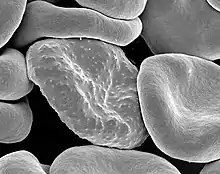

| Malaria parasite connecting to a red blood cell | |